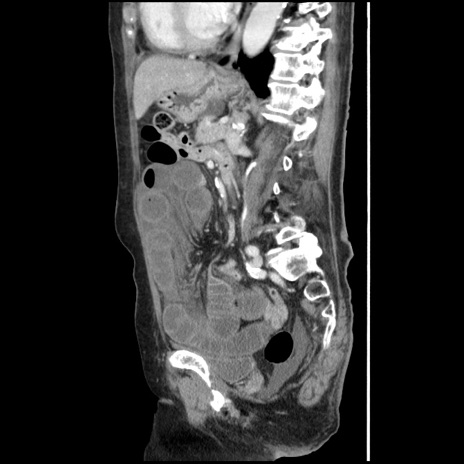

冠状断像

【症例】80歳代女性

【主訴】腹痛

【現病歴】8時間前から腹痛あり来院。

【既往歴】糖尿病、脂質異常症、子宮体癌にて子宮全摘術

【身体所見】意識清明・会話良好だが腹痛で苦悶様、全腹部にわたって反跳痛と圧痛あり

【データ】WBC 13600、CRP 0.14、LDH 224、CK 90